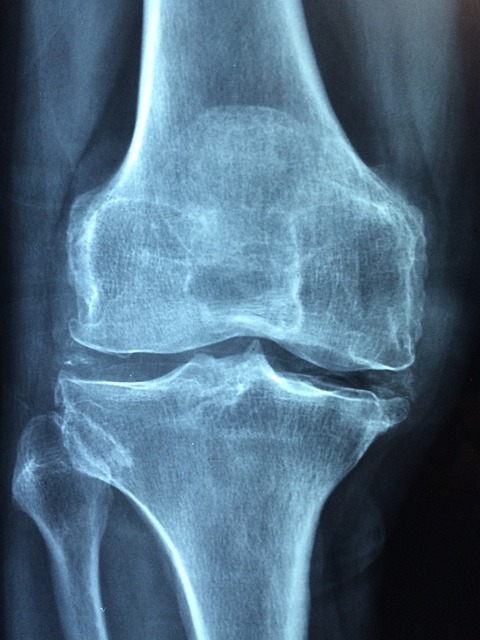

관절염은 염증이 관절에 생기는 질환이에요.

📌 특히 무릎·손가락 관절염은 체중이 늘거나 영양 균형이 깨지면 더 악화되기 쉬워요.

과체중은 무릎관절에 큰 압력을 줘요.

1kg만 감량해도 무릎에는 4kg의 부담이 줄어든다고 해요!